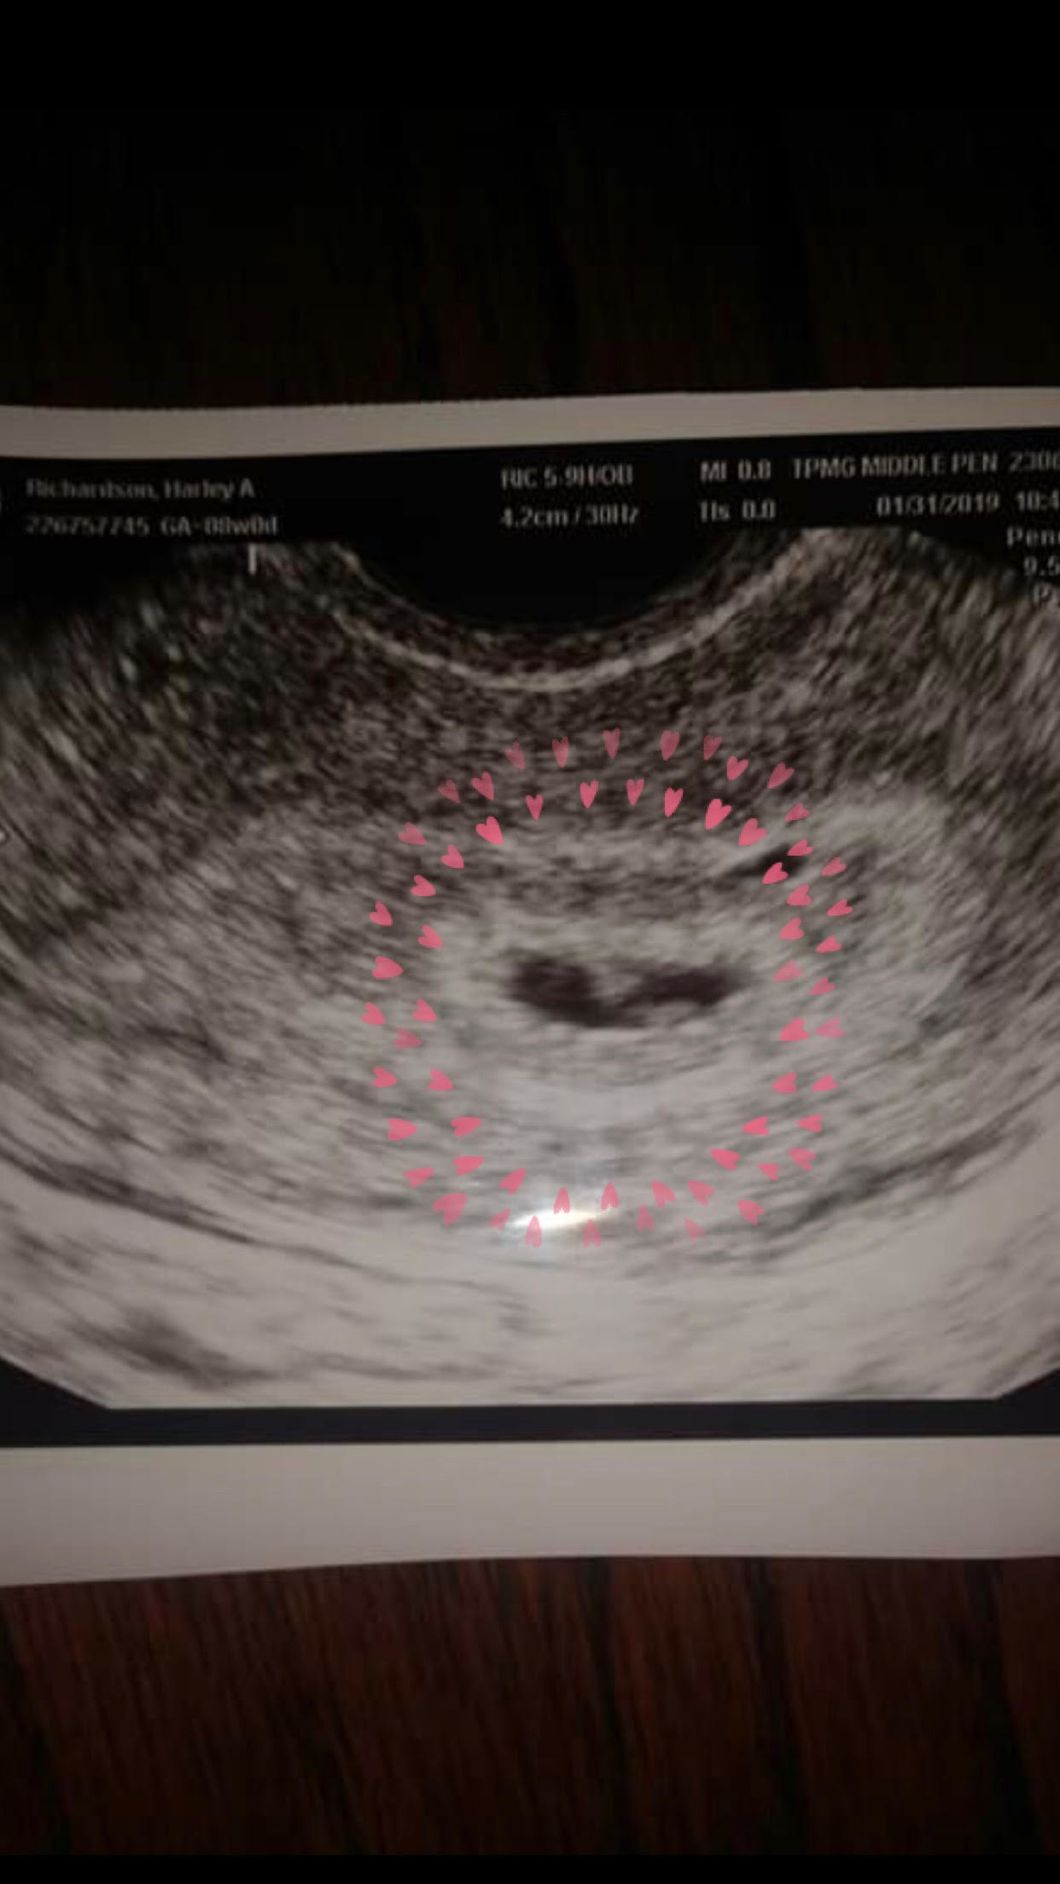

That is right, after two years of trying, my sister, Harley, is finally expecting her very first baby in September!